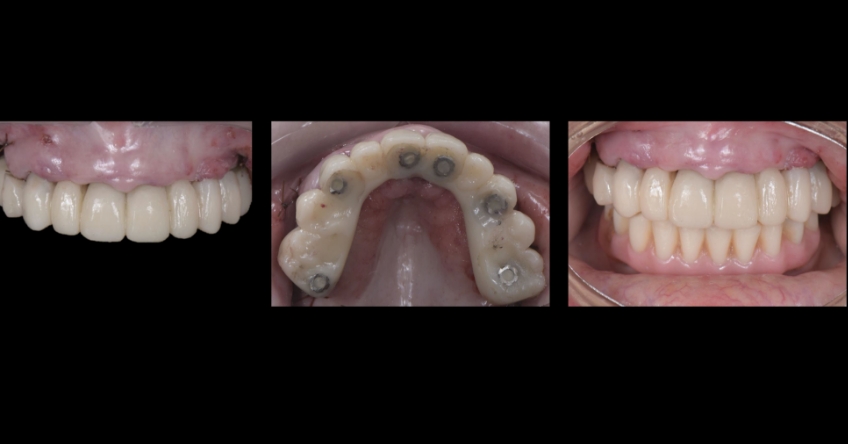

Even though there were only three remaining teeth, they were so severely compromised that they were hopeless; however, their presence, as well as the support provided by the flipper type of removable provisional restoration, helped enormously in preserving a rather pleasing gingival architecture, which would be destroyed if we chose a fixed-hybrid restoration.

This makes her a lip-tooth-ridge Class I patient according to the published classification. According to Dr. Mish’s classification, she is an FPI, which means her preexisting condition is conducive for an all-white, implant-supported fixed dental prosthesis without any pink ceramics.

Ultimately, the patient was treated using a combination of traditional and zygomatic implants, allowing her to transition into the definitive prosthesis uneventfully and in a reasonable time frame. This prosthetic design aimed to improve the distribution of occlusal forces and provide enhanced structural support for the final prosthesis.